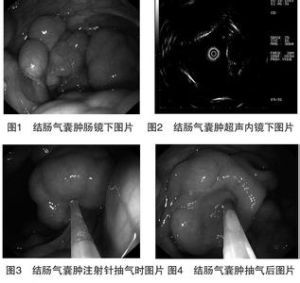

2.結腸鏡檢查結腸鏡可以明確病變性質。可見多個囊狀、葡萄狀隆起,表面略顯蒼白而透明囊性病變,大小可以從幾毫米到幾厘米。通常是軟的多發黏膜下病變突入腸腔,顏色可以發白或發藍,觸之軟弱而具彈性,活檢鉗或穿刺針刺破時可以因氣流從氣囊流出產生尖銳的“嘶”的聲音,而後氣囊塌陷。伴隨感染時囊腫表面及周圍黏膜可以出現炎性反應,表現不同程度的充血、水腫、糜爛等。

6.纖維結腸鏡下治療發現氣囊腫後,先用活檢鉗將氣囊腫夾破,然後將內鏡微波治療儀的同軸電纜通過內鏡活檢孔插入,電極頭伸出活檢孔3~4cm,並接觸囊腫進行凝固。微波輸出功率可用40w,每次2~3s,治療後局部黏膜呈灰白色凝固。此法具有組織損傷小、簡便、安全等優點。